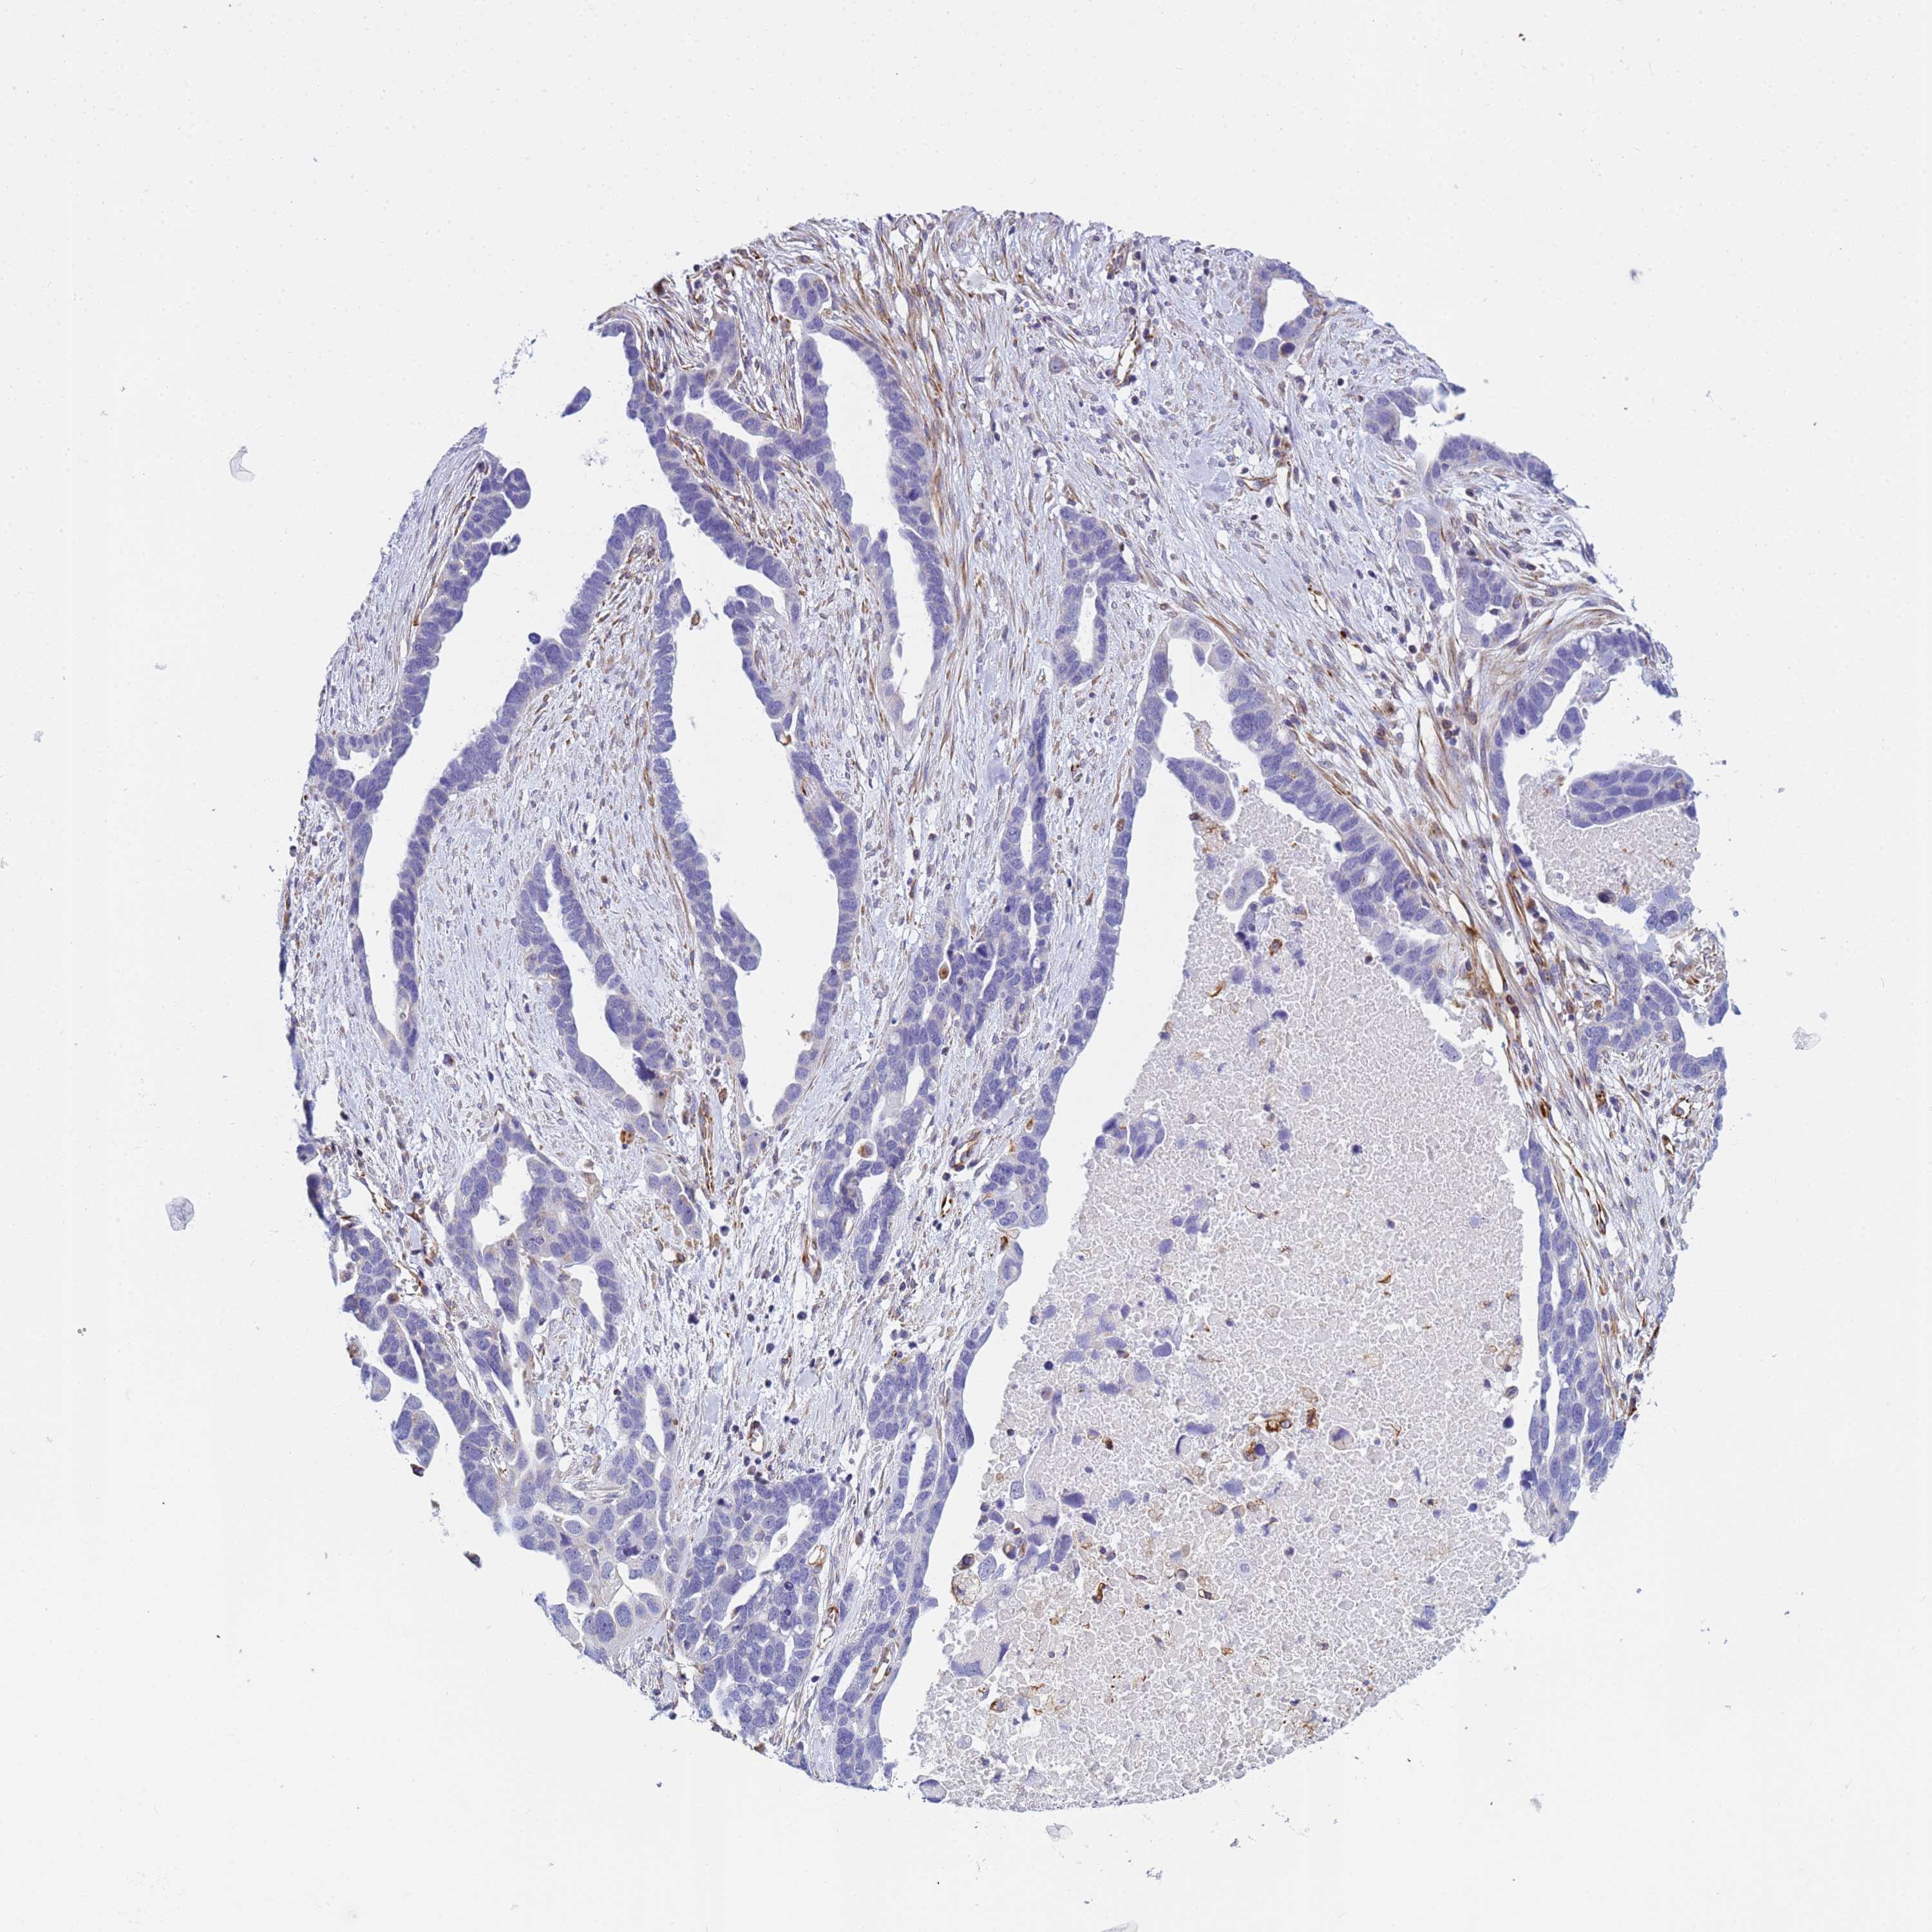

OVARIAN CANCER - Protein expressioni

A mouse-over function shows sample information and annotation data. Click on an image to view it in a full screen mode. Samples can be filtered based on level of antibody staining by selecting one or several of the following categories: high, medium, low and not detected. The assay and annotation is described here.

Note that samples used for immunohistochemistry by the Human Protein Atlas do not correspond to samples in the TCGA dataset.

Antibody stainingi

Antibody staining in the annotated cell types in the current human tissue is reported as not detected, low, medium, or high, based on conventional immunohistochemistry profiling in selected tissues. This score is based on the combination of the staining intensity and fraction of stained cells.

Each image is clickable and will lead to virtual microscopy that enables deeper exploration of all samples and also displays staining intensity scores, fraction scores and subcellular localization as well as patient and tissue information for each sample.

Antibody HPA045278

Staining

High

Medium

Low

Not detected

Intensity

Strong

Moderate

Weak

Negative

Quantity

>75%

75%-25%

<25%

None

Location

Nuclear

Cytoplasmic/membranous

Cytoplasmic/membranous,nuclear

Cystadenocarcinoma, serous, NOS

Carcinoma, endometroid

Cystadenocarcinoma, mucinous, NOS

Carcinoma, NOS